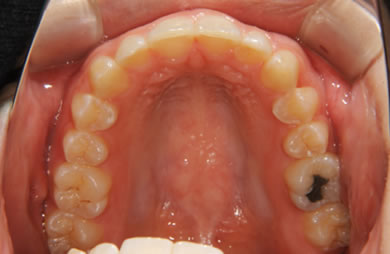

| 性別/年齢 | 女性 / 19歳 | ||||||||||||||||||||||||||||||||

| 主訴 | 上のデコボコの歯を綺麗にしたい。 | ||||||||||||||||||||||||||||||||

| 治療方針 | 上顎の歯の傾斜を正常に治す事で下顎を正常な位置に推進させ、非抜歯にて治療を行う。また、上下の顎のずれの治療のため、装置にゴムを使用し審美的・機能的に良い咬合を獲得させる。 | ||||||||||||||||||||||||||||||||

| 治療内容 | 唇側矯正(シルバー) | ||||||||||||||||||||||||||||||||

| 総治療費 | 659,300円 | ||||||||||||||||||||||||||||||||

| 治療期間 | 1年9ヶ月 |